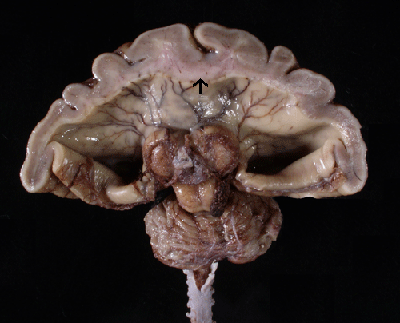

Alobar Holoprosencephaly: Note there is no separation of the cerebral hemispheres into left and right. The cardinal diagnostic feature is the extension of gray matter across the midline (arrow).